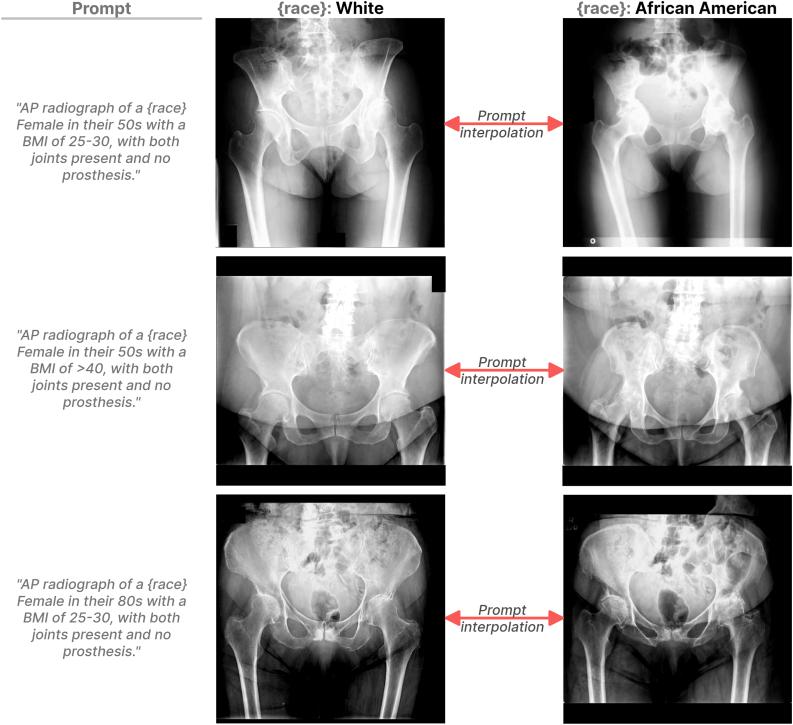

METHODS

Utilizing a large institutional registry, we retrospectively analyzed pelvic radiographs from total hip arthroplasty patients, characterized by demographics and image features. Denoising diffusion probabilistic models generated radiographs conditioned on demographic and imaging characteristics. Fréchet Inception Distance assessed the generated image quality, showing the diversity and realism of the generated images. Sixty transition videos were generated that showed transforming White pelvises to their closest African American counterparts and vice versa while controlling for patients' sex, age, and body mass index. Two expert surgeons and 2 radiologists carefully studied these videos to understand the systematic differences that are present in the 2 races' radiographs.

RESULTS

Our data set included 480,407 pelvic radiographs, with a predominance of White patients over African Americans. The generative denoising diffusion probabilistic model created high-quality images and reached an Fréchet Inception Distance of 6.8. Experts identified 6 characteristics differentiating races, including interacetabular distance, osteoarthritis degree, obturator foramina shape, femoral neck-shaft angle, pelvic ring shape, and femoral cortical thickness.